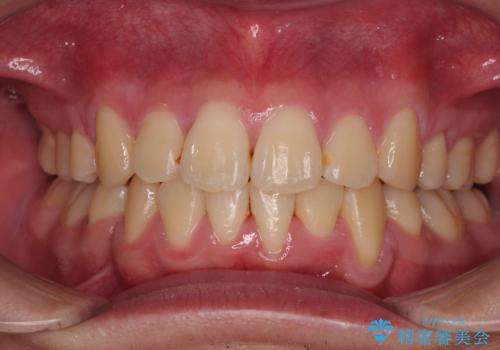

移動が順調に進み、1年半の短期間で治療を終えることができました。

前方に突出した上顎前歯の傾斜も改善されました。